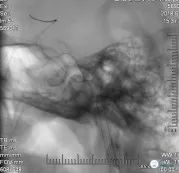

并反复抽吸多功能导管,抽出一2*3mm致密斑块(图9)

抽瘪球囊,再次多功能导管手推造影:未见明显游离血栓影,仍无明显前向血流(图10)